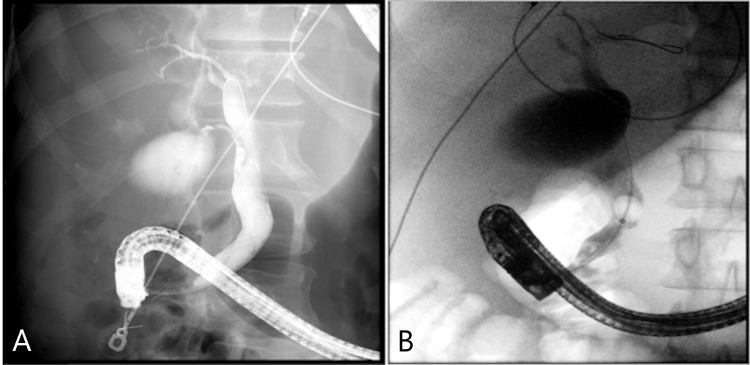

He was brought back to a medical facility one month after his discharge. He was found to have a fever of 38.3 °C, tachycardia, and hypotension. His initial blood work showed leukocytosis with a WBC count of 19 x 109/L, alkaline phosphatase of 870 U/L (normal range: 30-135 U/L), alanine aminotransferase (ALT) of 77 U/L (normal range: 10-55 U/L), and bilirubin of 1.3 mg/dL. His ultrasound showed cholelithiasis and a dilated common bile duct (CBD) (9 mm). An echogenic focus consistent with a stone was noted in the distal CBD on ultrasound. Repeat COVID-19 polymerase chain reaction (PCR) testing was negative twice. He was diagnosed with cholangitis and was resuscitated with 5 L of crystalloids and broad-spectrum antibiotic coverage. He progressed to septic shock and was stabilized on norepinephrine with improvement in his serum lactate. He was transferred to our institution for a higher level of care and consideration of performing an endoscopic retrograde cholangiopancreatography (ERCP). His CT scan upon arrival showed a moderately distended gallbladder. There was mild gallbladder wall thickening and pericholecystic fluid consistent with acute cholecystitis. In line with the ultrasound findings, several tiny stones in the distal CBD were found (Figure 1). His anticoagulation was held for 24 hours prior to his ERCP.

ERCP confirmed a distal linear filling defect within the lower CBD (Figure 2). Interestingly, there was CBD dilation without intrahepatic duct dilation (Figure 3). A sphincterotomy and balloon sphincteroplasty were performed. The linear bile duct stone in the shape of a bile duct cast was extracted using balloon sweep. There was mild oozing from his sphincterotomy, and hence his bile duct was stented given the need for the resumption of anticoagulation. A bile duct aspirate grew Staphylococcus epidermidis. After the procedure, his condition was found to be good with improvement in his liver enzymes. His antibiotics were deescalated to oral medications and his diet was advanced. His acute cholecystitis was managed with antibiotics. General surgery reviewed his case and offered an outpatient cholecystectomy.

A repeat outpatient ERCP was performed for stent removal. During this exam, his stents and further bile duct casts were removed. However, the second ERCP was indicative of significant intrahepatic ductal disease (Figure 4). He was evaluated by hepatology and diagnosed with SSC-CIP. Primary sclerosing cholangitis, congestive hepatopathy, and other causes of secondary sclerosing cholangitis were excluded.